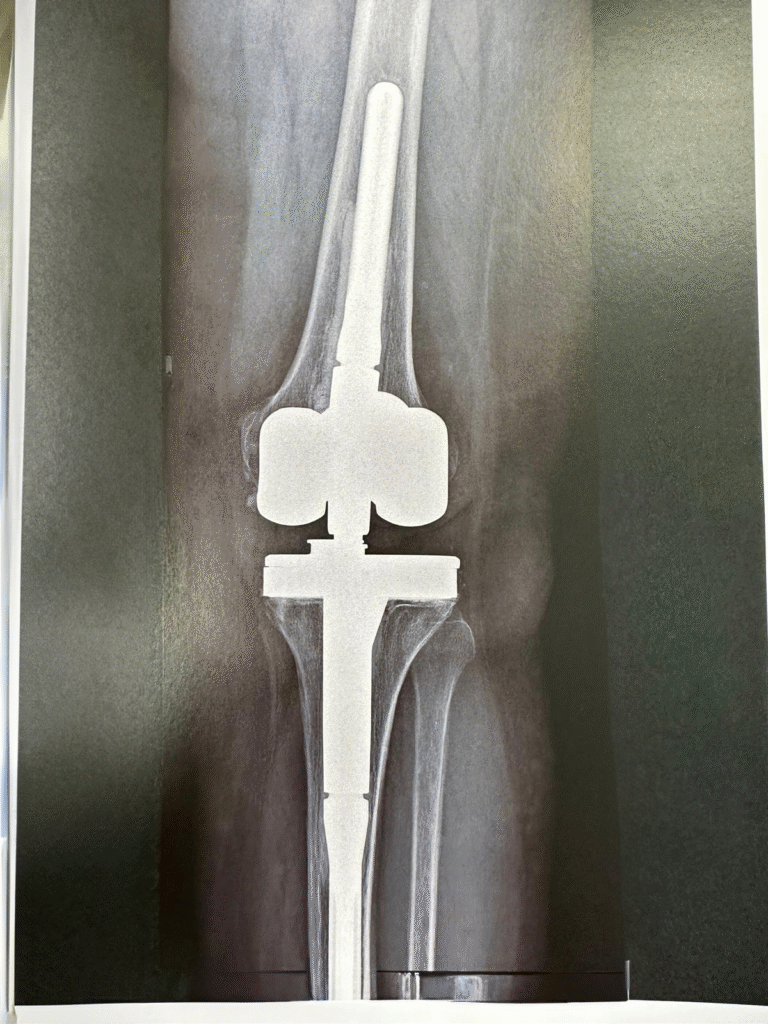

PROTHÈSE DE GENOU

L’opération consiste à enlever le cartilage usé et quelques millimètres d’os puis à recouvrir les surfaces osseuses du fémur et du tibia par du métal séparé par un insert en polyéthylène (plastique chirurgical) qui permet le glissement. En général la rotule sera amincie et recouverte d’un bouton en polyéthylène.

Il existe de nombreux type de prothèses de genou, votre chirurgien choisira celle qu’il pense adaptée à votre situation.

Comment s'organise une prothèse totale de genou (PTG) ?

Le chirurgien effectue une incision (ouverture) de la peau de taille variable en fonction de votre cas, en général située sur le devant du genou. L’articulation est ouverte et nettoyée des débris de cartilage et des becs osseux dus à l’arthrose. Puis il va faire les coupes : celle du tibia est plate celles du fémur sont plus complexes pour reproduire la forme de l’os.

On effectue ensuite des essais pour s’assurer de la bonne tension des ligaments puis les pièces prothétiques vont être fixées à l’os en général par une résine nommée ciment chirurgical

REPRISE DE PROTHÈSE DE GENOU

La prothèse de genou est une intervention très fréquente en France (80 000).